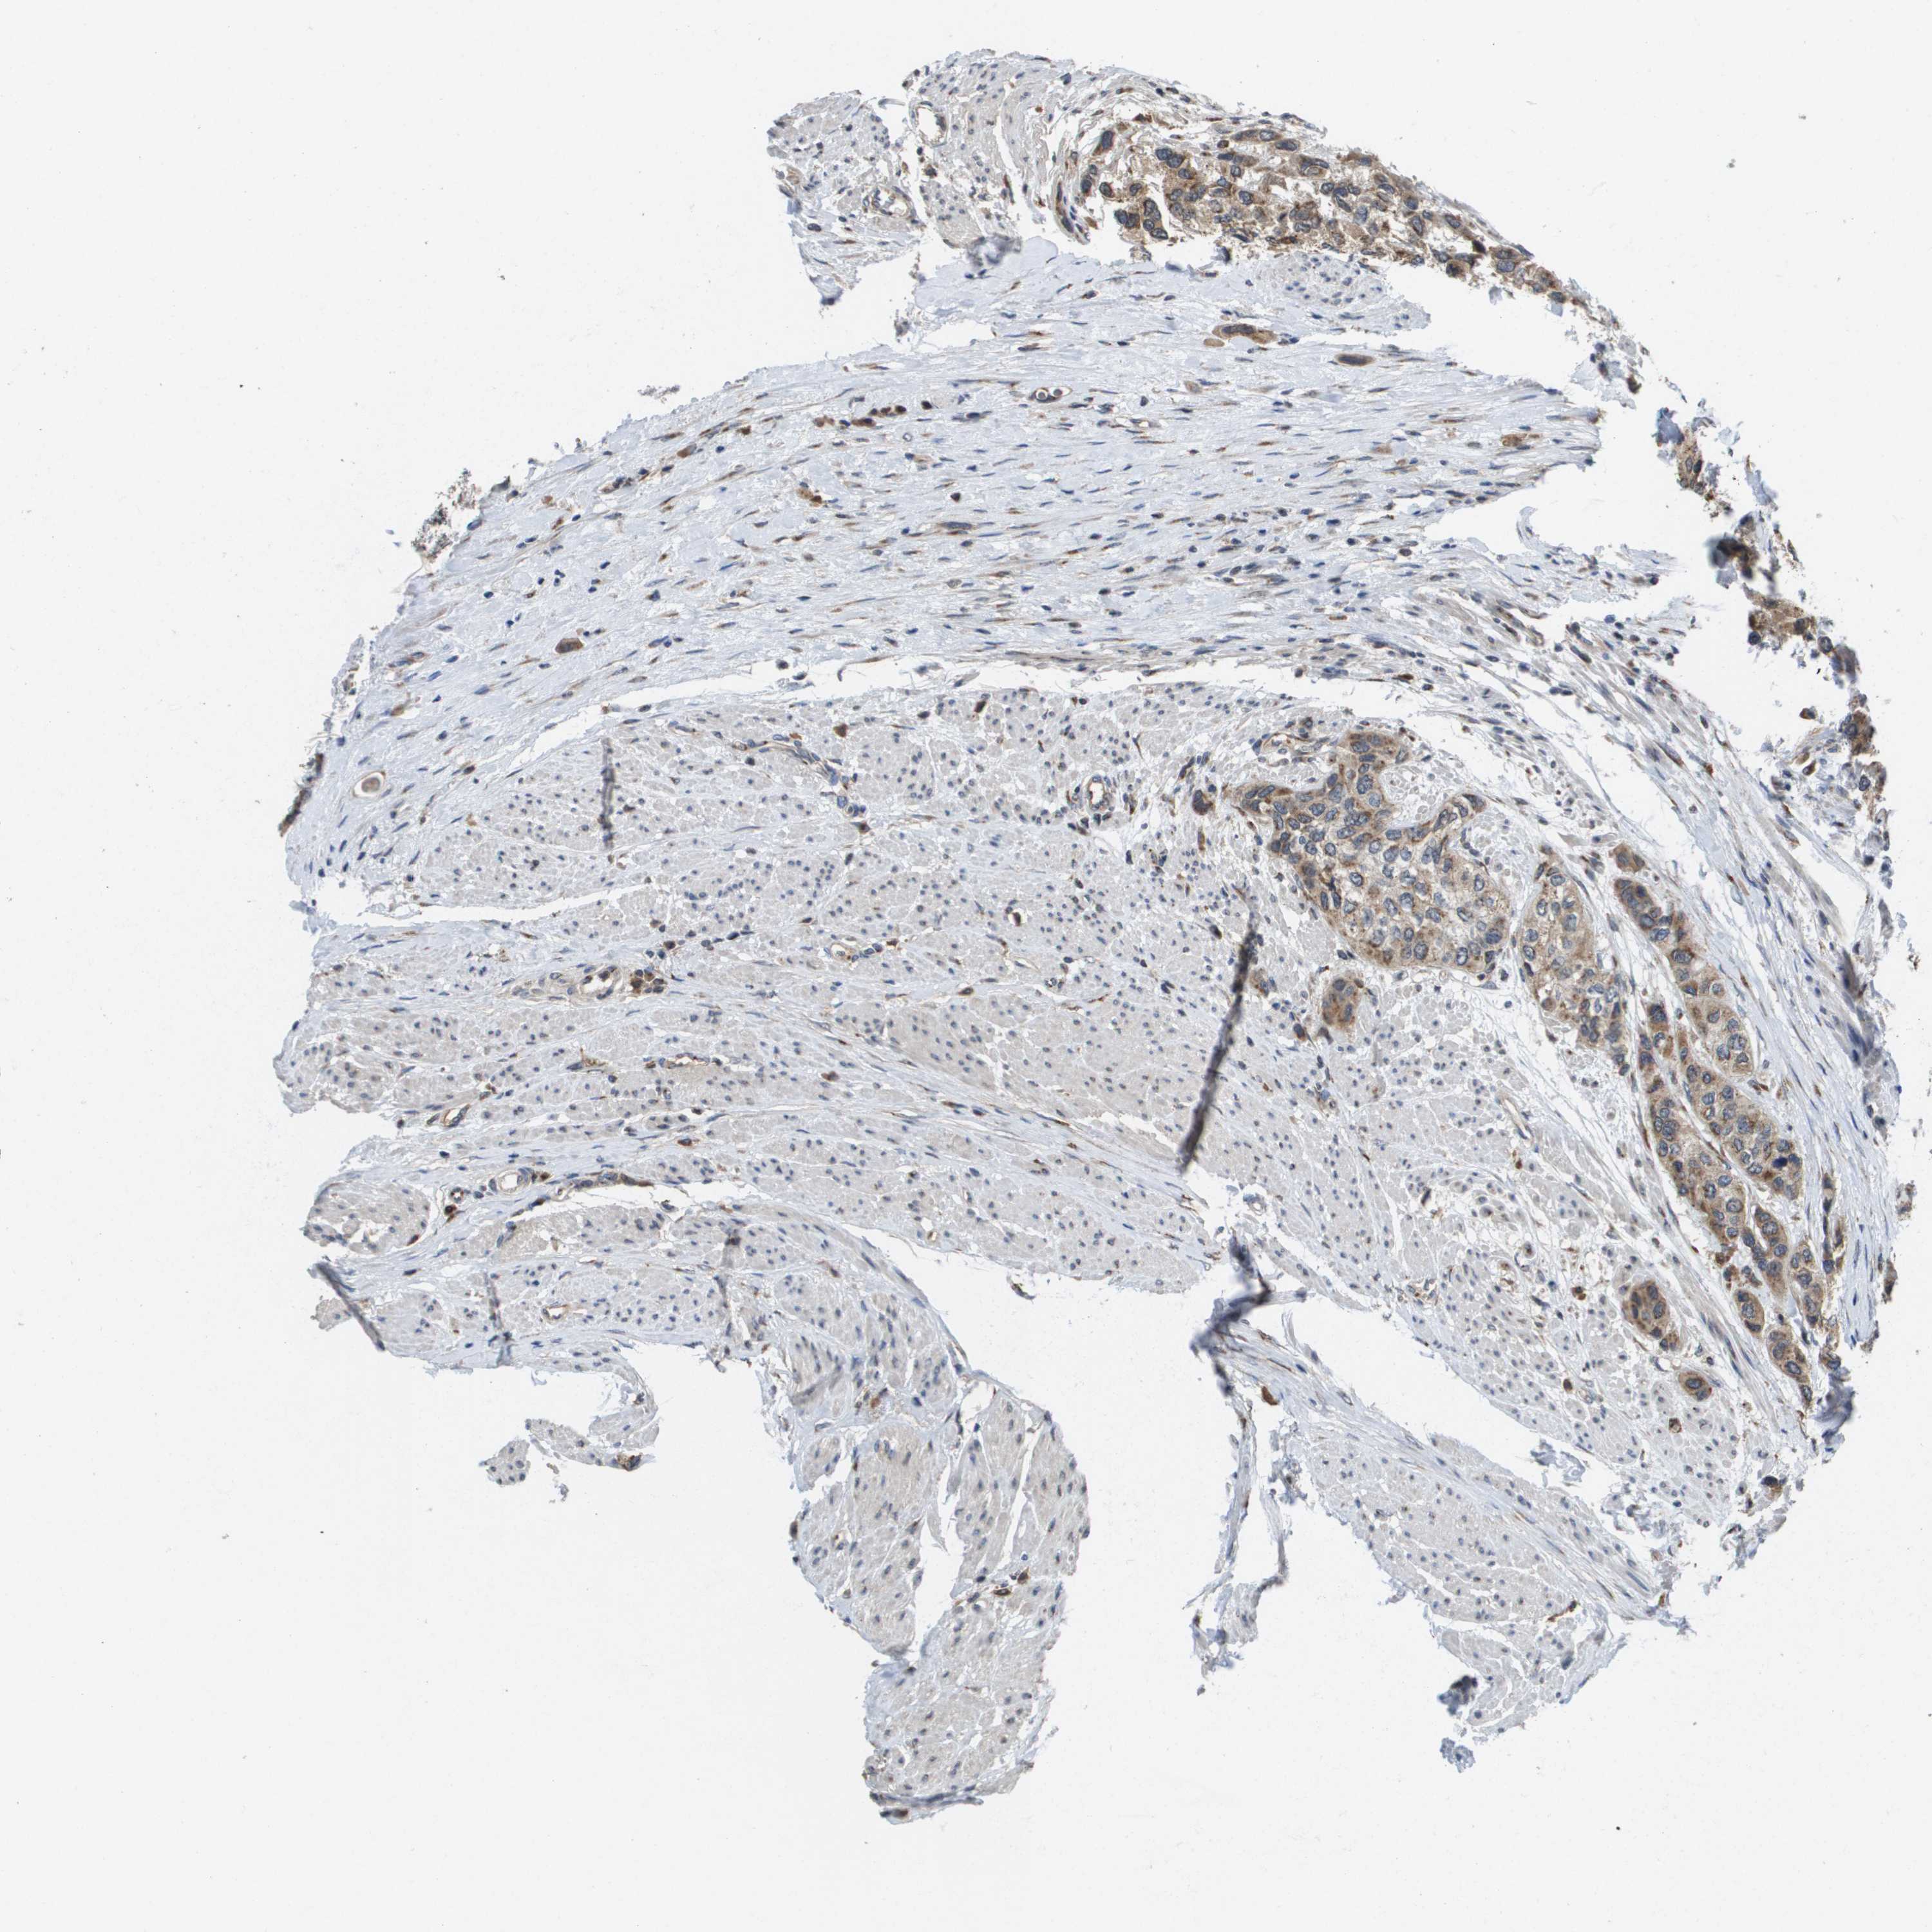

UROTHELIAL CANCER - Protein expressioni

A mouse-over function shows sample information and annotation data. Click on an image to view it in a full screen mode. Samples can be filtered based on level of antibody staining by selecting one or several of the following categories: high, medium, low and not detected. The assay and annotation is described here.

Note that samples used for immunohistochemistry by the Human Protein Atlas do not correspond to samples in the TCGA dataset.

Antibody stainingi

Antibody staining in the annotated cell types in the current human tissue is reported as not detected, low, medium, or high, based on conventional immunohistochemistry profiling in selected tissues. This score is based on the combination of the staining intensity and fraction of stained cells.

Each image is clickable and will lead to virtual microscopy that enables deeper exploration of all samples and also displays staining intensity scores, fraction scores and subcellular localization as well as patient and tissue information for each sample.

Antibody HPA006277

Antibody HPA006507

Antibody CAB017027

Staining

High

Medium

Low

Not detected

Intensity

Strong

Moderate

Weak

Negative

Quantity

>75%

75%-25%

<25%

None

Location

Nuclear

Cytoplasmic/membranous

Cytoplasmic/membranous,nuclear

Urothelial carcinoma, Low grade

Urothelial carcinoma, High grade